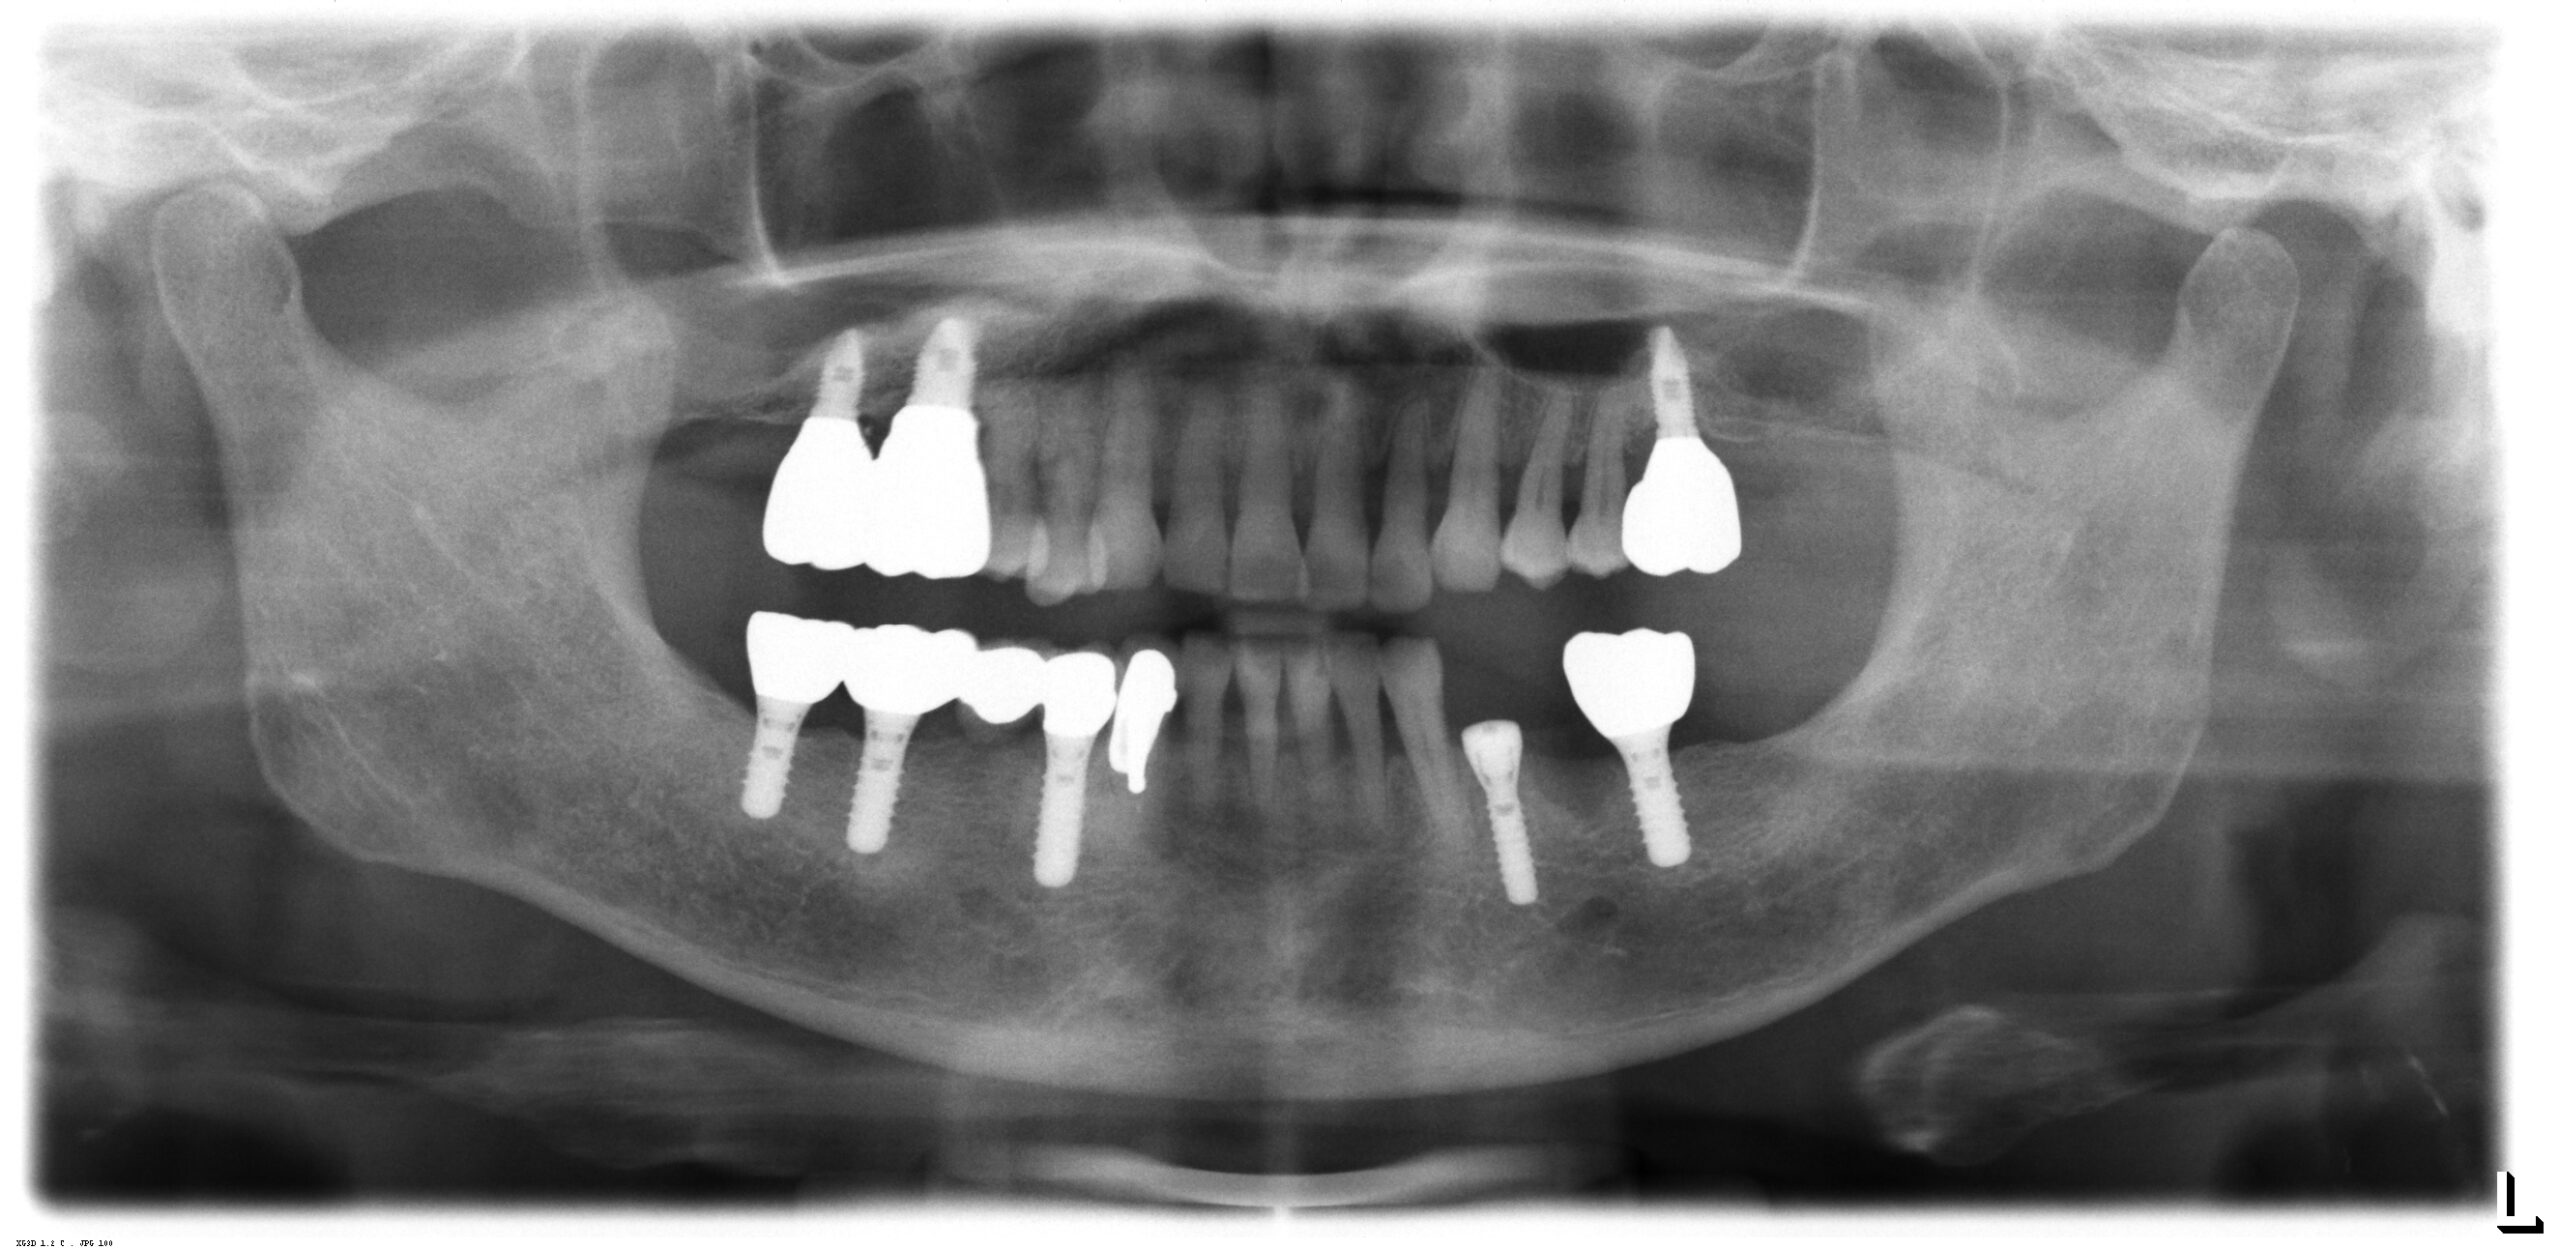

左下に今回1本のストローマンインプラントを埋入した後のレントゲンです。

さらに今年になって左下の小臼歯の歯周病が進行して抜歯となり、本日第1小臼歯部位にストローマンTL 3.3 12mmを埋入しました。

2か月後に第1大臼歯部位のインプラントと連結して、ブリッジがはいる予定です。